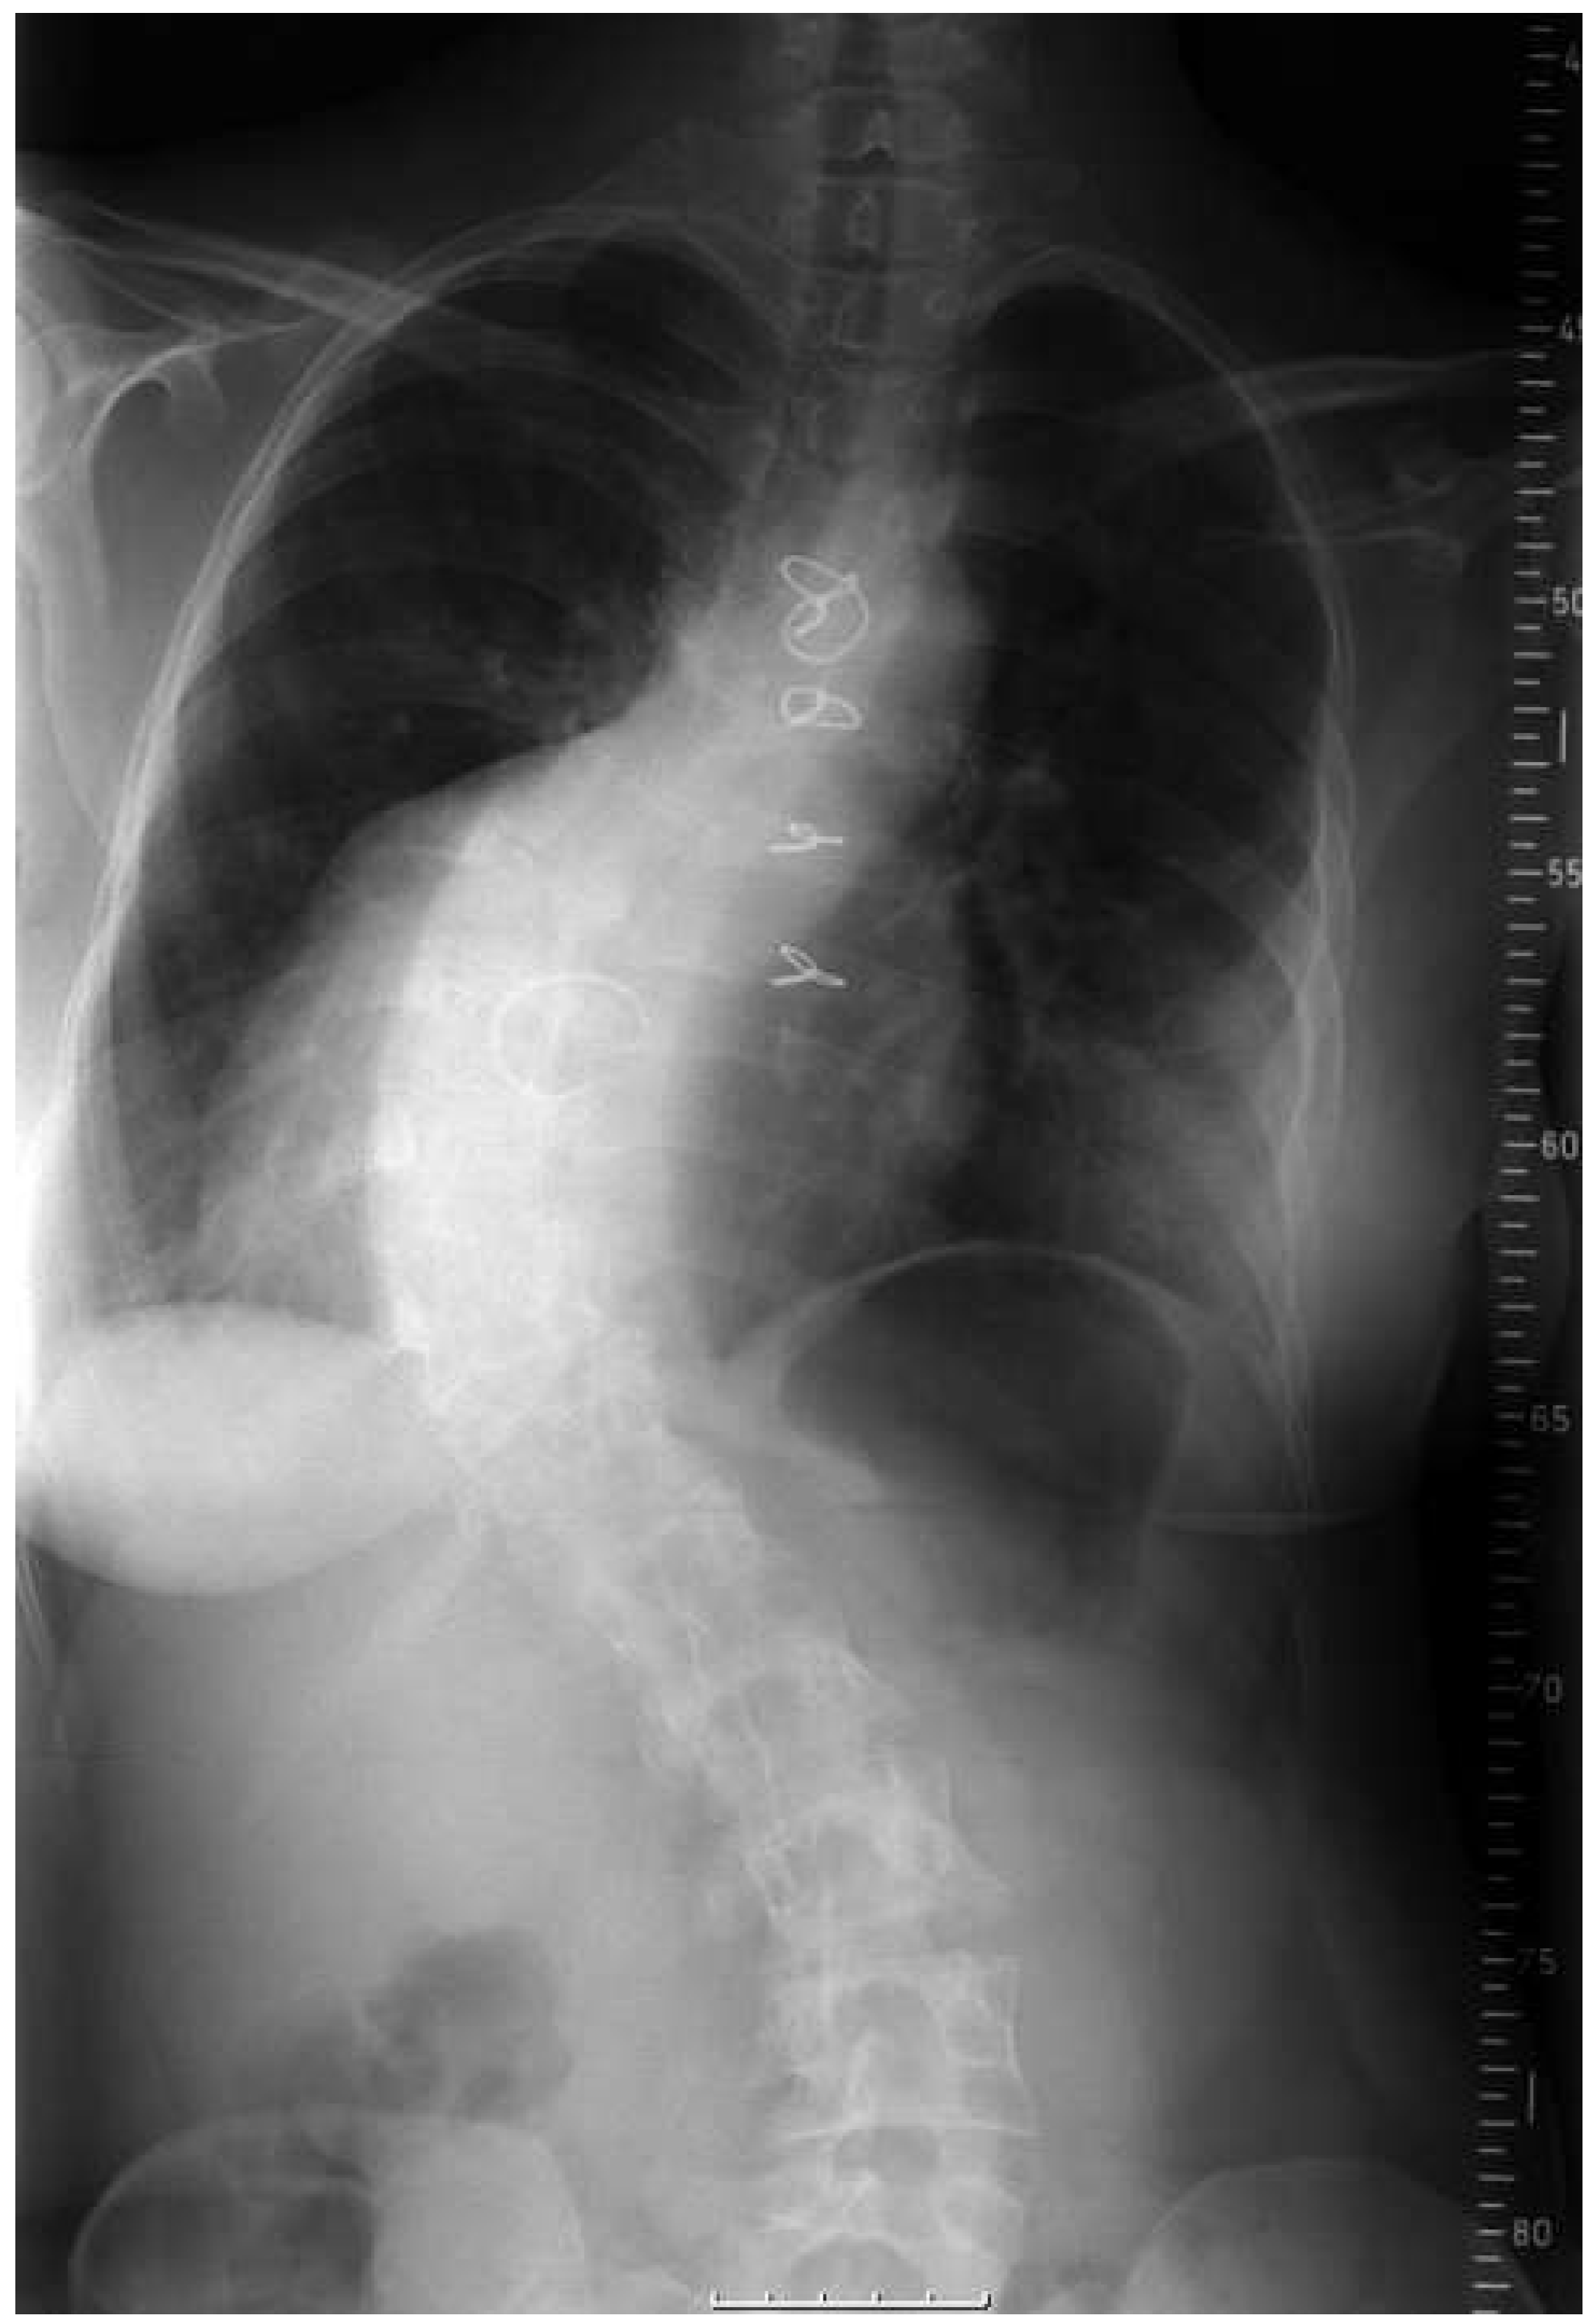

Abbildung 1. Bei dieser 28-jährigen Patientin mit korrigierter Fallot-Tetralogie, Dextrokardie und Arcus aortae dexter besteht zusätzlich eine schwere Skoliose, die atemmechanisch zu einer mittelgradigen Restriktion führt. Die Leistungsfähigkeit in der Spiroergometrie ist mittelschwer eingeschränkt, es besteht eine gemischt pulmonale und kardiale Limitation der Leistungsfähigkeit.